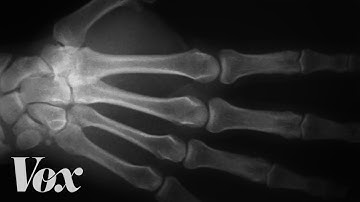

What Happens If You Bite Down on a Finger?